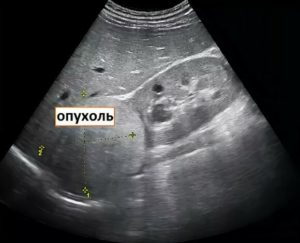

Такой вид имеет раковое поражение почки на УЗИ. Источник: delaiuzi.ru

Многие пациенты интересуются, как выглядит на УЗИ рак почки. Специалисты отвечают, что злокачественных новообразований довольно много, причем они могут значительно отличаться друг от друга. Наиболее известной является аденокарцинома. Во время скрининга она выражена в форме темного пятна, в особенных случаях имеющего белые перегородки.

Поскольку формирование содержит вкрапления солей кальция, они просматриваются как белые пятна. Эта опухоль характеризуется стремительным ростом, который отчетливо виден при динамическом контроле. Также аденокарцинома за короткое время может давать вторичные очаги (метастазы), поэтому необходимо обследовать и другие органы.

- Аденокарцинома – раковая опухоль почки, выглядящая на УЗИ, как темное пятно округлой формы, иногда разделённое светлыми перегородками. Стенка новообразования неровная и тонкая. Внутри часто видны светлые участки–кальцинаты, образованные солями кальция. Опухоль быстро растет, что хорошо видно на повторном УЗИ. Поскольку новообразование быстро дает метастазы, больным нужно обследовать и другие органы, в первую очередь — печень и легкие.